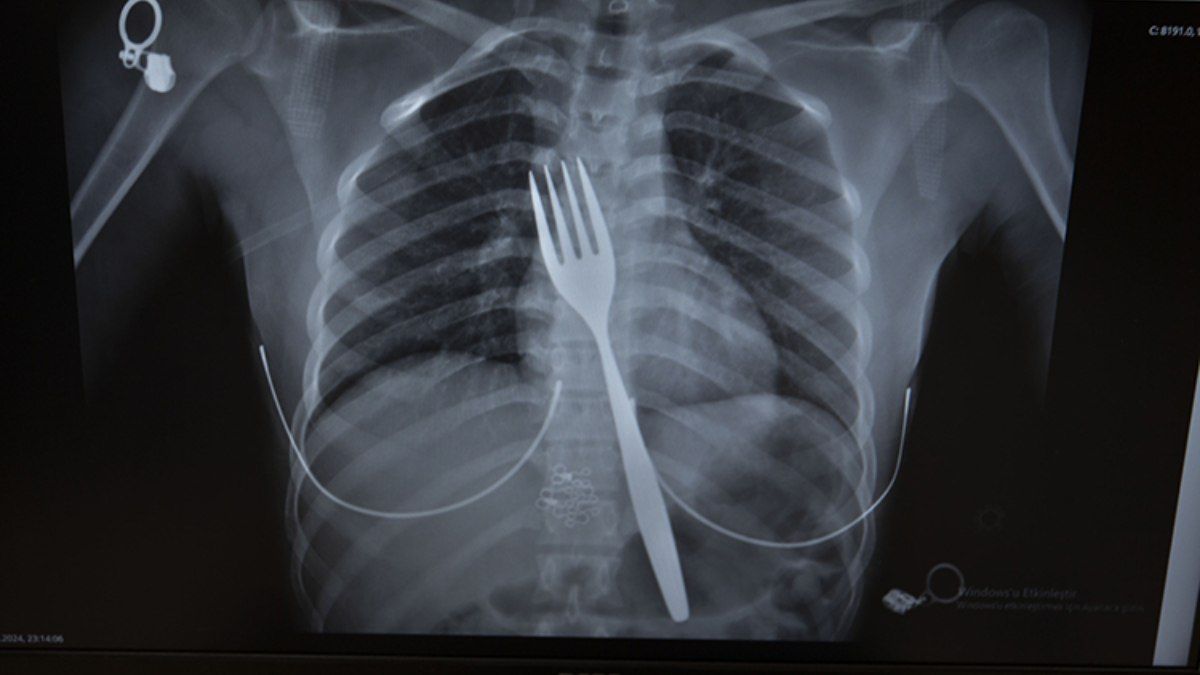

Aydın’da 18 santimlik çatal yuttu

Söke ilçesinde bir genç kızın yuttuğu 18 santimetrelik çatal, operasyonla alındı. Bu operasyon hakkında bir bilimsel makale yazılmasına karar verildi.